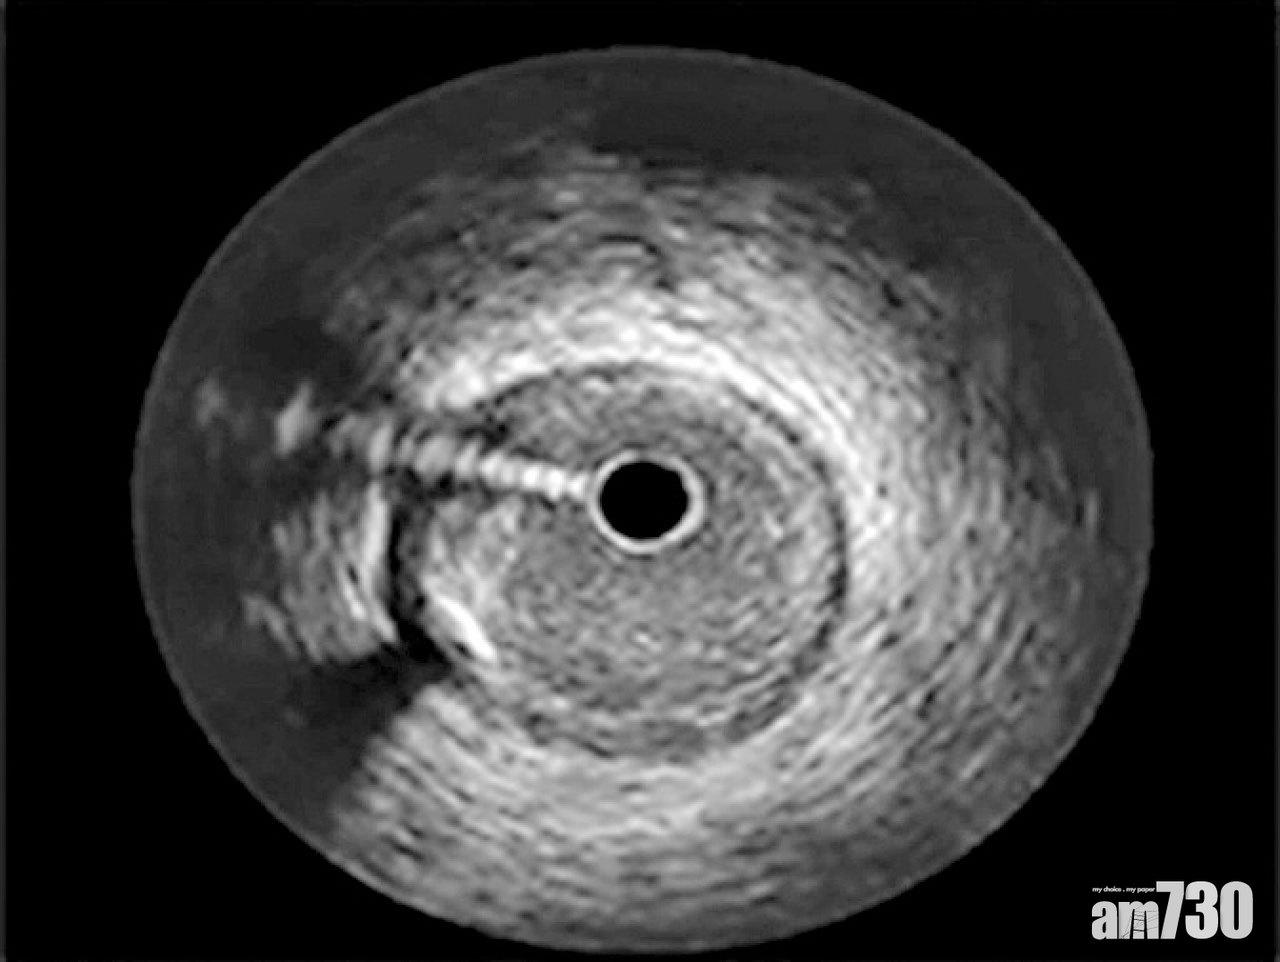

除了診斷,現時的微創血管治療,例如靜脈曲張手術、血管穿刺等,以超聲波導引去進行,已經是不可缺少的標準技術,甚至手術期間,可以超聲波的導管,在血管內作「血管腔內超聲波」(Intravascular Ultrasound)檢查,準確地看到血管收窄的程度。